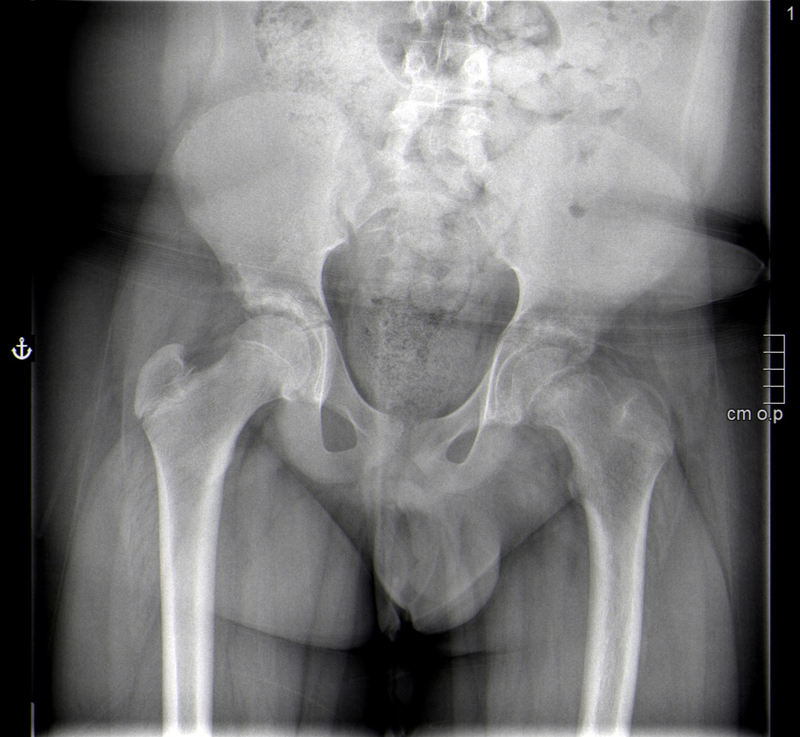

Vi­no por dis­ne­a… y le o­pe­ra­ron la ca­de­ra

Paciente de 13 años que consulta por una dudosa sensación de disnea. Afebril, sin clínica de enfermedades infecciosas. A la exploración destaca obesidad y ausencia de signos de distrés respiratorio, con auscultación cardiopulmonar normal. Llama la atención una marcha antiálgica del paciente, que precisa la ayuda de muletas. Por anamnesis dirigida refiere gonalgia izquierda de mes y medio de evolución coincidente con un papiloma en el pie contralateral. En la exploración de los miembros inferiores presenta una marcada limitación a la rotación interna y la flexión de la cadera izquierda, con exploración de la rodilla normal.